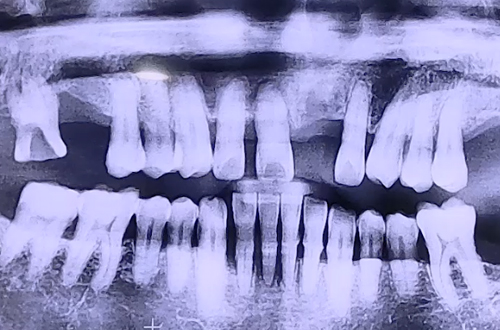

BEFORE

앞 치아들이 많이 흔들리는 상태로 내원하신 환자분입니다.

앞니 3개 중 한 개는 이미 많이 흔들리다 집에서 저절로 빠졌다고 하셨는데요.

정확한 치아 상태를 알기 위해 CT검진을 해 보니,

입천장 쪽 잇몸의 뼈는 괜찮은 편이었지만 바깥쪽 잇몸 뼈들이 완전히 녹아있던 상태였습니다.

잇몸이 약해진 부분, 이가 저절로 빠진 자리와 그 양 옆 흔들림이 있는 2개 치아까지